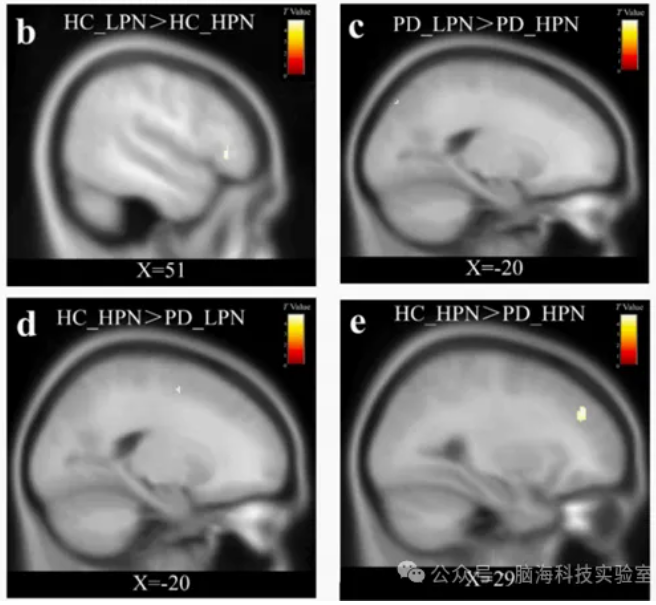

多模态脑影像数据分析平台